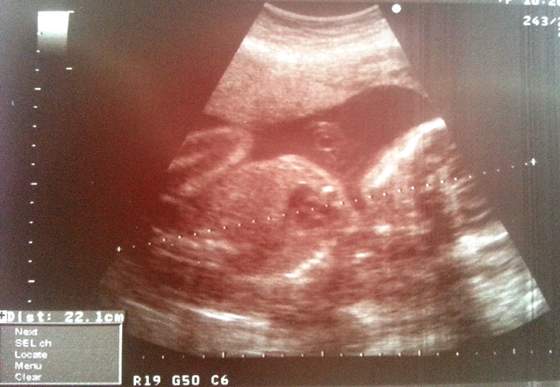

Wymiary (Matyldy rzecz jasna

):

wymiar dwuciemieniowy, czyli średnica główki BPD 68mm

obwód główki HC 244mm

obwód brzuszka AC 211mm

długość kości udowej FL 46mm

waga 932g

długość bez nóg 22cm, z nogami szacunkowo ok 40cm

wymiarowo jest większa o ok 1 tydzień, TP wg USG: 19.05.2013

Gin chciała nam buźkę pokazać ale mała nie chciała współpracowac i się pokazać